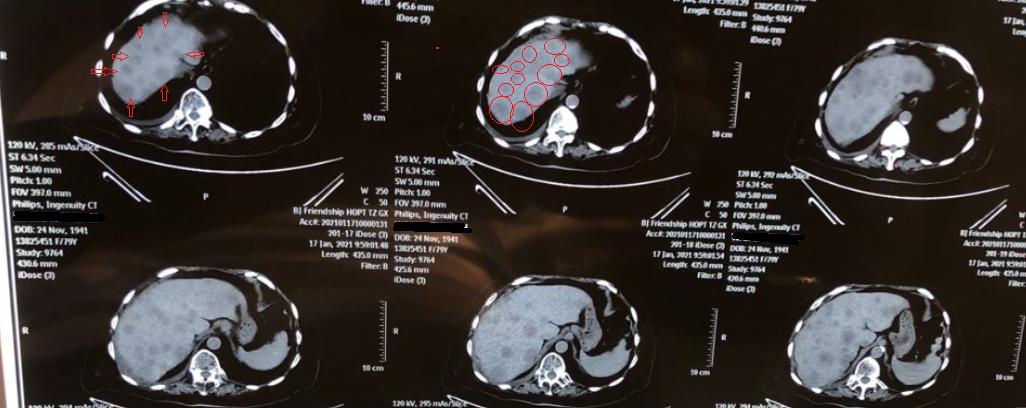

Recently, another patient with liver metastasis of cancer came to the outpatient clinic. Looking at the CT scan, my heart sank. The primary lesion itself wasn’t too problematic, but there were too many liver metastases. Just in one cross-section of the CT scan, more than ten visible metastatic foci could be seen.

Late-stage detection is very easy, as seen with the patient mentioned at the beginning of the article, where both the symptoms and the findings on the CT scan are quite obvious. However, in the early stages, when the lesions are small, diagnosis is relatively difficult.

CT is a relatively precise examination method for diagnosing liver metastatic tumors, with higher sensitivity than ultrasound. However, it may miss tiny lesions.